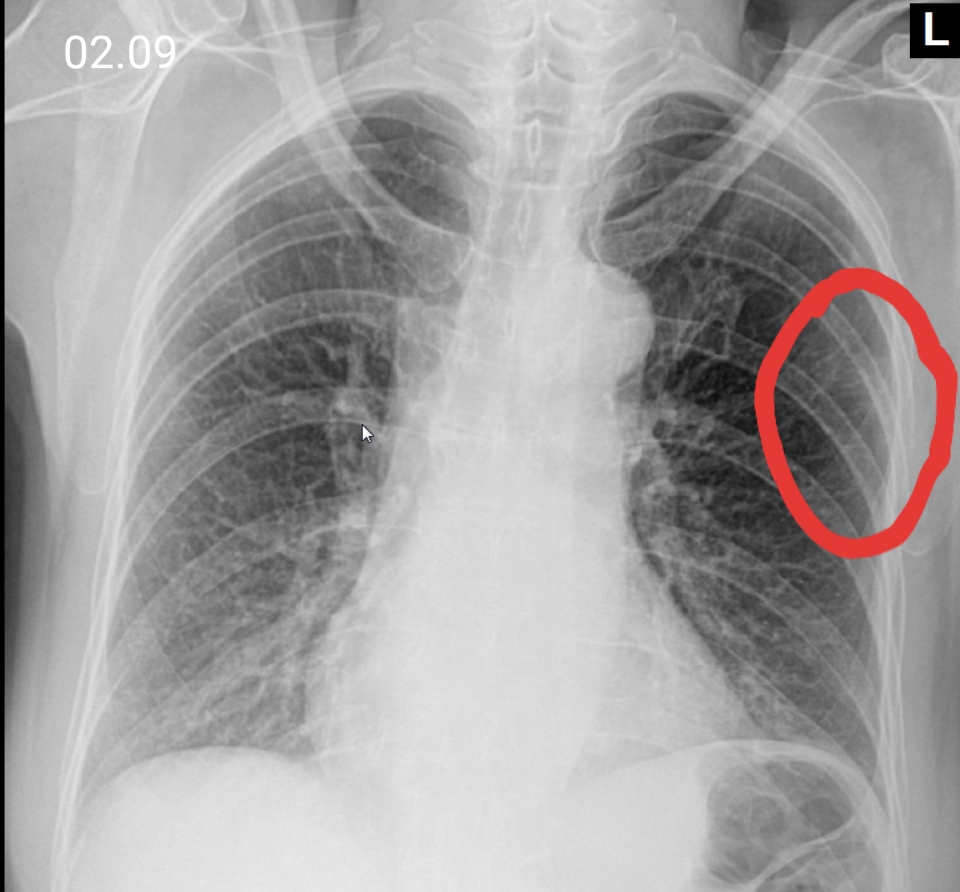

Нормальная рентгенограмма легких: что нужно знать

Раздел: Мудрость в объективе